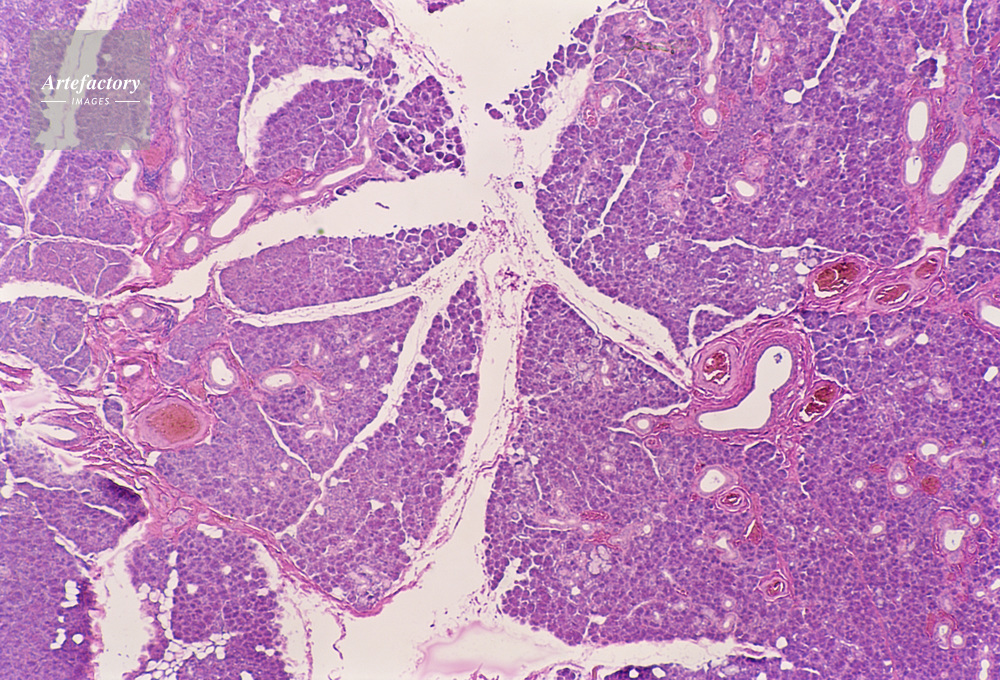

| キャプション | 下顎線,人間,20倍 | 制限事項 | ||